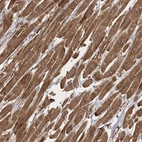

Immunohistochemical staining of human heart muscle shows moderate cytoplasmic positivity in myocytes.